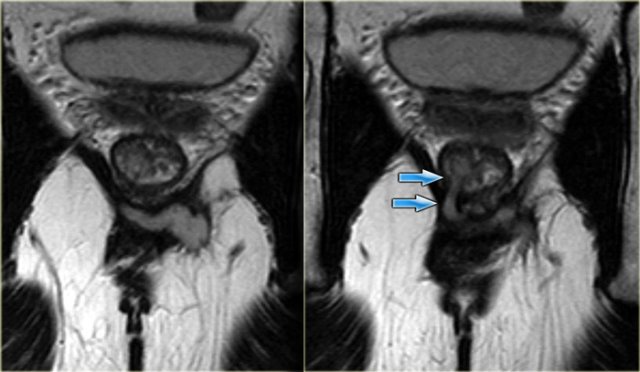

Transsphincteric fistula

On the left an axial T2WI and T2WI + fatsat of a transsphincteric fistula.

The defect through the internal and external sphincter at 6 o'clock is clearly visible and more apparent on the fat sat images.

Transsphincteric fistula with sphincter defect at 11 o'clock Transsphincteric fistula with sphincter defect at 11 o'clock

On the left axial T2W-fatsat images of a transsphincteric fistula with the mucosal opening at 11 o'clock.